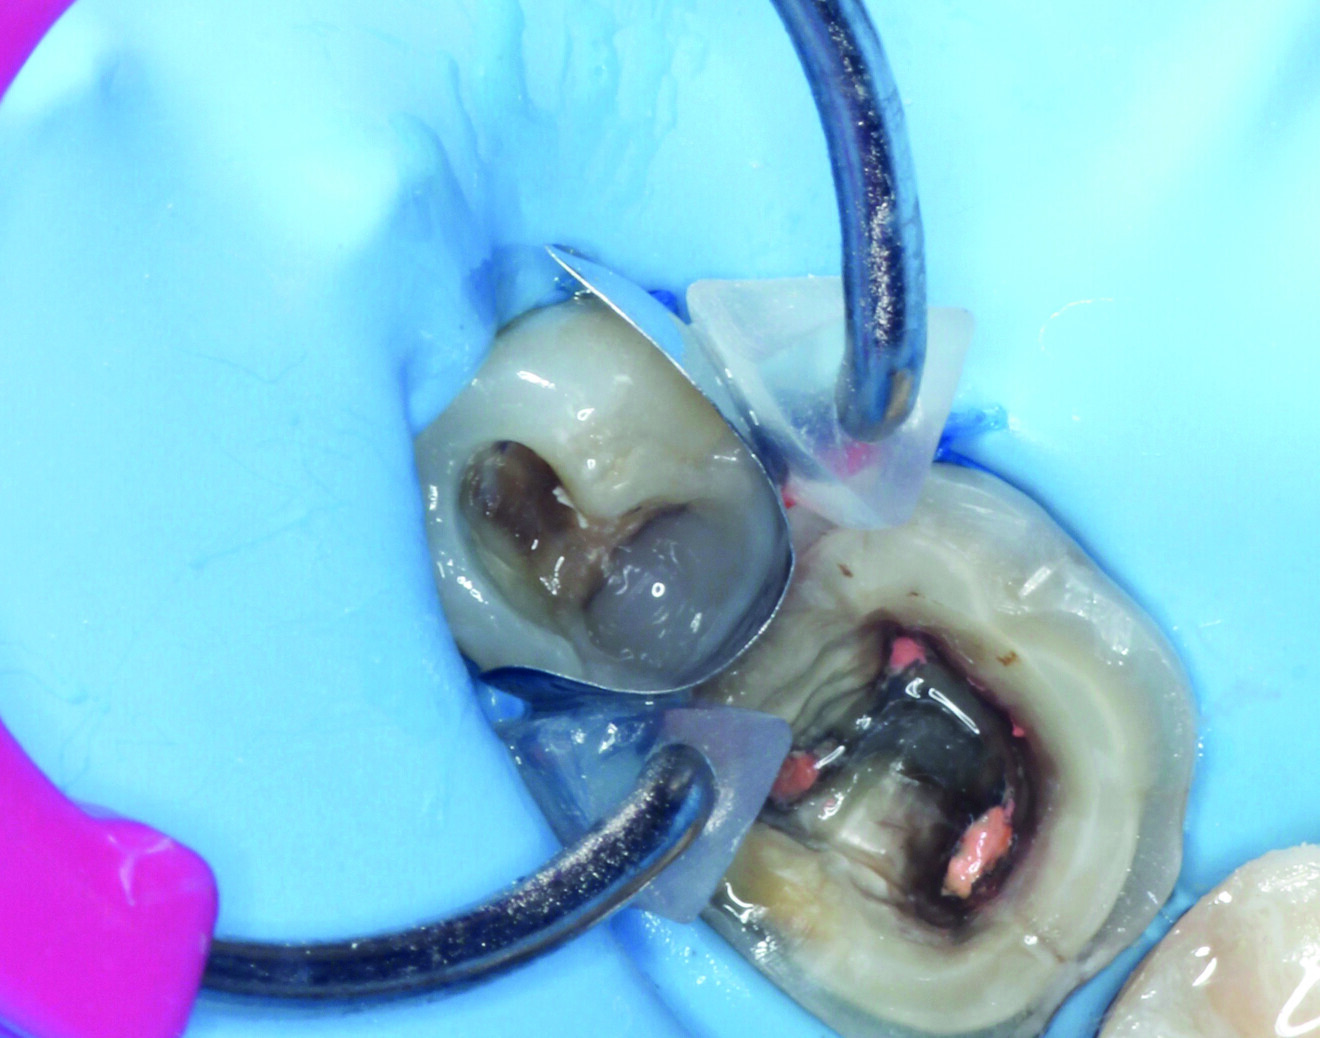

Fig. 2: Dental dam isolation for removal of the old restoration from tooth #45 using ultrasonic instrumentation.

Fig. 3: Matrix system positioned for correct adaptation of the margin on tooth #45.

After the removal of the old fillings and isolation with a dental dam (Nic Tone) to achieve a dry working field, the treatment was performed on the two teeth (Fig. 2). A W8 clamp hook (Hu-Friedy) was used to keep the dental dam in place. The sectional matrix was stabilised along the axial distal wall of the cavity of tooth #45 using Unimatrix R (TDV Dental; Fig. 3).